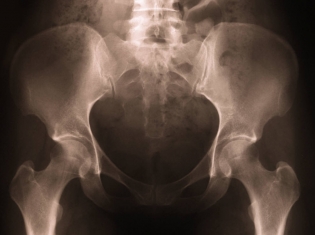

(RxWiki News) A total hip replacement can reduce pain and bring back mobility. Still, the procedure has its complications, requiring some patients to go in for an additional surgery, called a revision.

According to a recent study, age and body size may impact the risk of revision of total hip replacement. Results showed that patients who were taller, heavier or 75 years of age and younger had increased odds of revision.